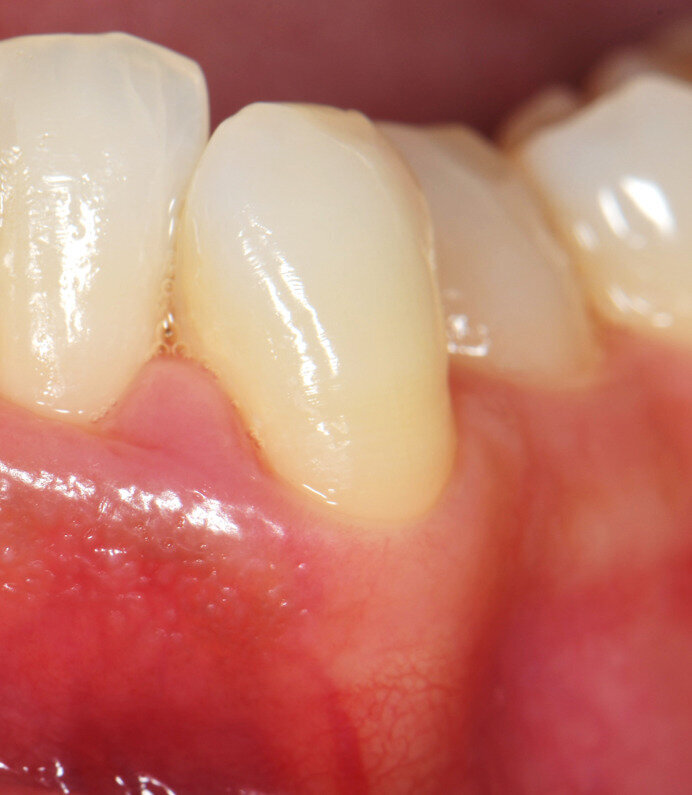

Fig. 3 - Caso clinico illustrativo. Visione frontale del difetto iniziale. I tessuti appaiono edematosi, la papilla interdentale è rigonfia e distaccata dalle superfici dei denti contigui.

Fig. 4 - Sondaggio parodontale. PPD di 6 mm e CAL di 7 mm per l’elemento 33.